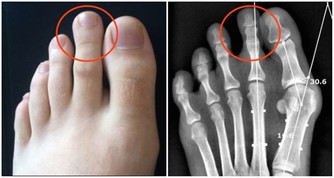

而長期存在漏藥,少服一類地打亂用藥規律的行為,就相當於身體存在長時間的血壓波動,尤其對於腎臟來說,入球小動脈以及小葉間動脈發生炎症的概率增加,出現慢性腎病甚至腎衰竭的概率也會無限增大,還請一定要注意。